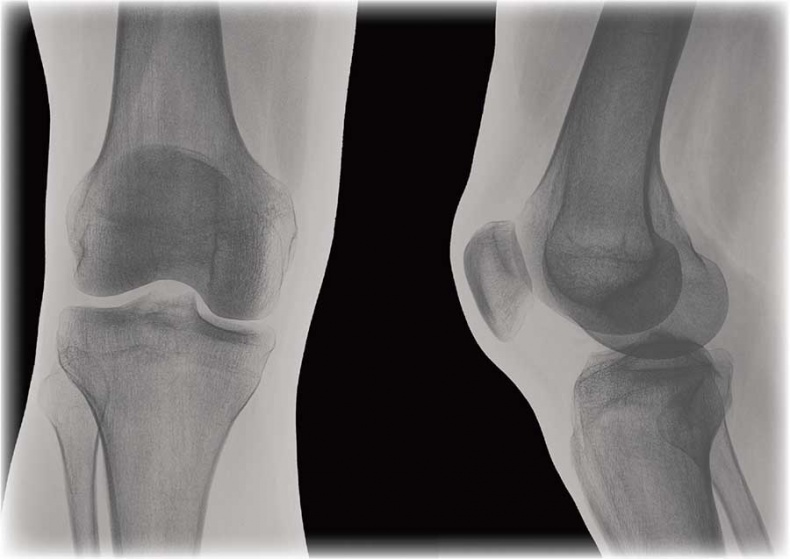

Соединение костей в коленном суставе (вверху – рентген, внизу – модель)

Суставные поверхности костей, образующие сустав, плотно прилегают друг к другу. Они покрыты особым гиалиновым хрящом, чья гладкая поверхность и эластичность облегчают движение в суставе, смягчают испытываемые им толчки и сотрясения.

Суставные поверхности костей окружает суставная капсула – оболочка из соединительной ткани. Обычно она крепится к костям в месте перехода суставной поверхности в надкостницу и прочно с ней срастается. Снаружи капсула укреплена связками, которые располагаются в местах наибольшей нагрузки.

Суставные поверхности и капсула ограничивают собой небольшое герметично закрытое пространство – полость сустава, заполненную малым количеством вязкой синовиальной жидкости, роль которой заключается в уменьшении трения в суставах при движении. Благодаря отрицательному давлению в суставной полости поверхности костей тесно прилегают друг к другу.